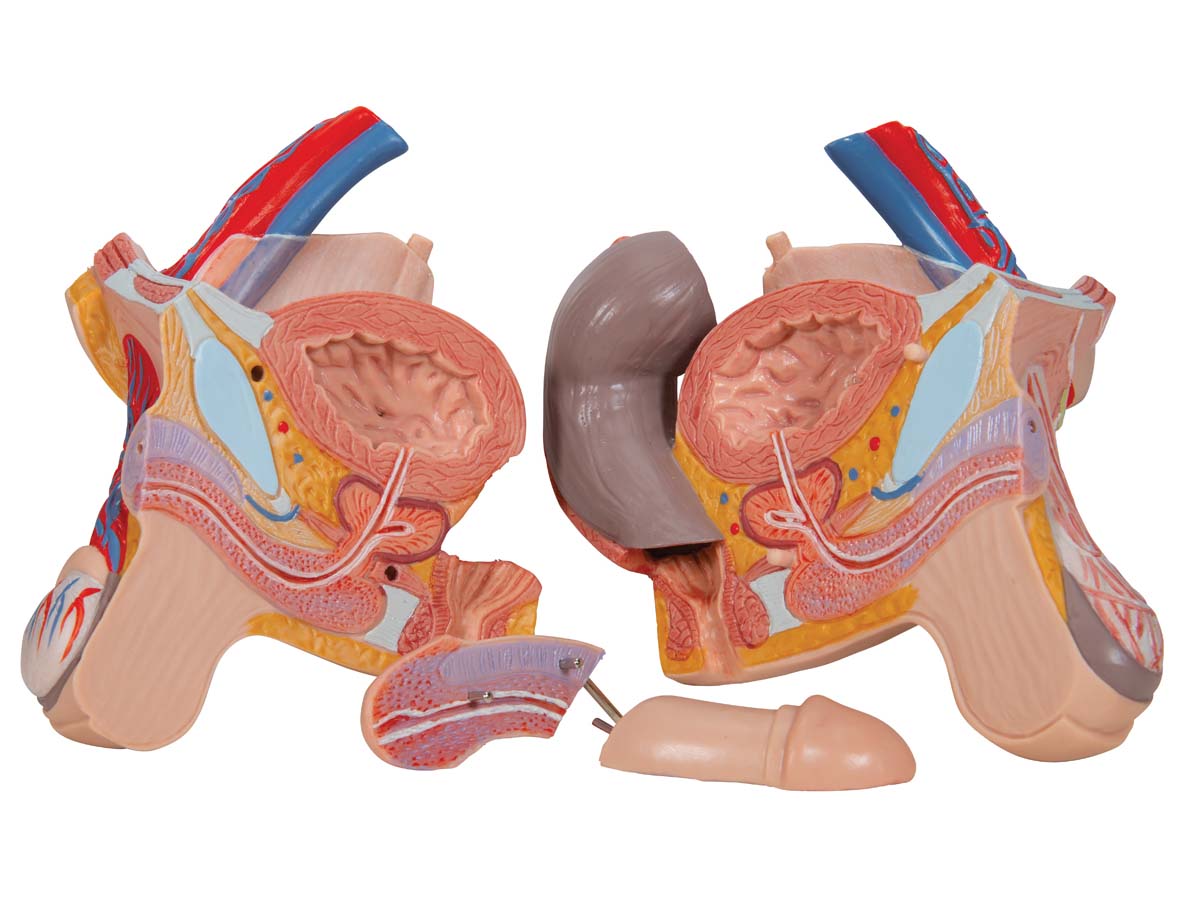

Luxus Torso Modell, mit weiblichen & männlichen Geschlechtsorganen, 24-teilig

Luxus Torso Modell, mit weiblichen & männlichen Geschlechtsorganen, 24-teilig – 3B Smart Anatomy

Der 3B Scientific Luxus-Torso bietet Ihnen alle Möglichkeiten für ausführliche Demonstrationen. Sie erhalten hunterprozentige Qualität und einen hohen Grad an Detailarbeit. Die Beschaffenheit der erweiterten Torso-Version ist beeindruckend, genau wie sein Preis! Beantworten Sie mit seiner Hilfe alle Fragen zur inneren Anatomie des Menschen. Er ist zerlegbar in:

– 4-teiliger männlicher Genitaleinsatz

Alle Organe in diesem menschlichen Torso sind von Hand bemalt.

7. Möglichkeit zum Erlernen der männlichen und weiblichen Anatomie